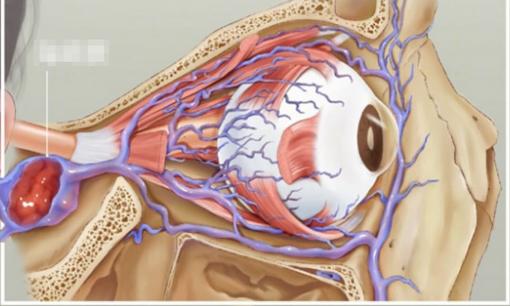

Bé trai 8 tuổi ngoáy mũi đưa vi khuẩn vào não, thói xấu dọa giết người, vùng tam giác mũi miệng không thể ngờ được

Cậu bé 8 tuổi không biết từ bao giờ đã hình thành thói quen thích ngoáy mũi, bố mẹ buông lỏng quản lý, khi chưa...